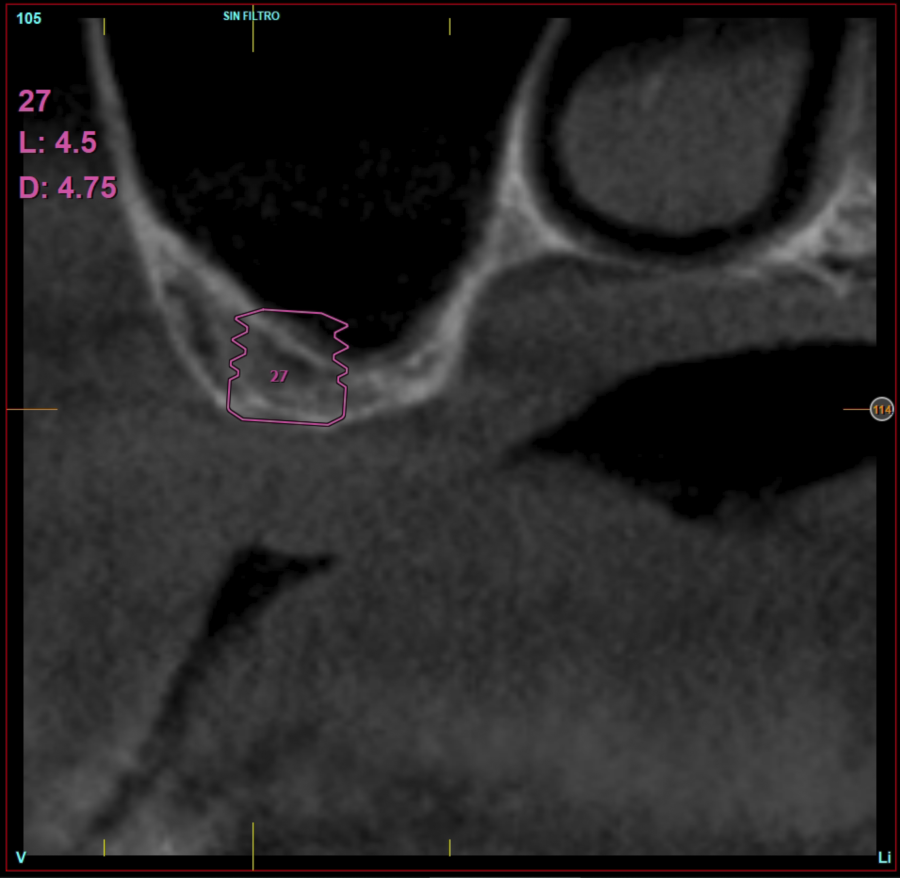

Ten patients who met the inclusion criteria were recruited, in which 20 implants were inserted. Three of them were women with an average age of 72 (+/- 6 years). None of the patients were smokers at the time of surgery and did not have any active periodontal disease. The majority of the implants diameter included in the study was 5 mm (60%), followed by 4.5, 5.5 and 4.75 mm (13.33% each). The predominant length was 5.5 mm (86.6% of the cases), with 13.4% of the remaining implants with a length of 4.5 mm. The most common positions were for the second molars (molars 27 and 17) representing 55% of the cases.

Figures 2-19 show one of the cases included in the study.